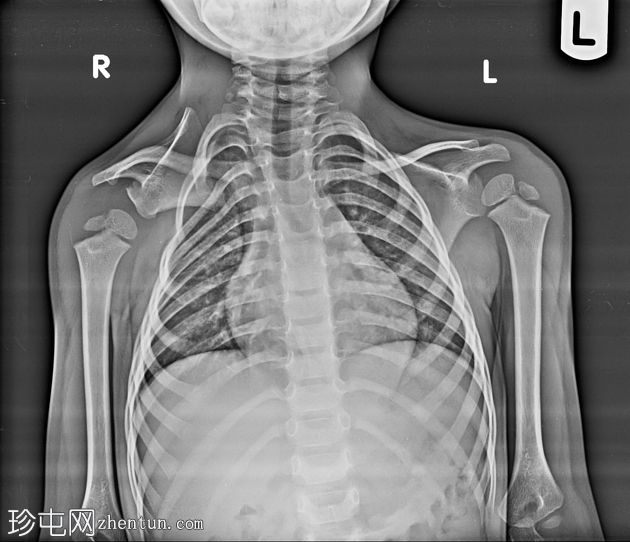

Sprengel肩

右肩位置异常

年龄:3岁

性别:男

X线片

右侧肩胛骨位置较高,高于预期位置,呈垂直方向,符合Sprengel畸形。右侧肋骨方向/角度轻度改变,可能继发于肩胛骨位置异常和慢性畸形。肩肱关节和肩锁关节结构正常。未见急性骨折或局灶性破坏性病变。锁骨影像正常。

双侧肩关节正位X线片中,肩胛骨高度和方向的显著差异应高度怀疑先天性肩胛骨异常,例如Sprengel畸形。

检查肋骨和胸廓是否存在继发性改变(角度、扭曲),这些改变可能反映长期的生物力学适应。

始终与对侧进行比较,以评估不对称性。